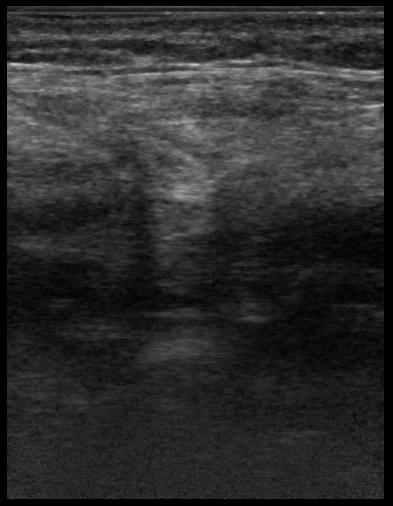

17-летняя девушка с множественными поражениями печени

абсцесс передней брюшной стенки (через 2 недели п.о.)